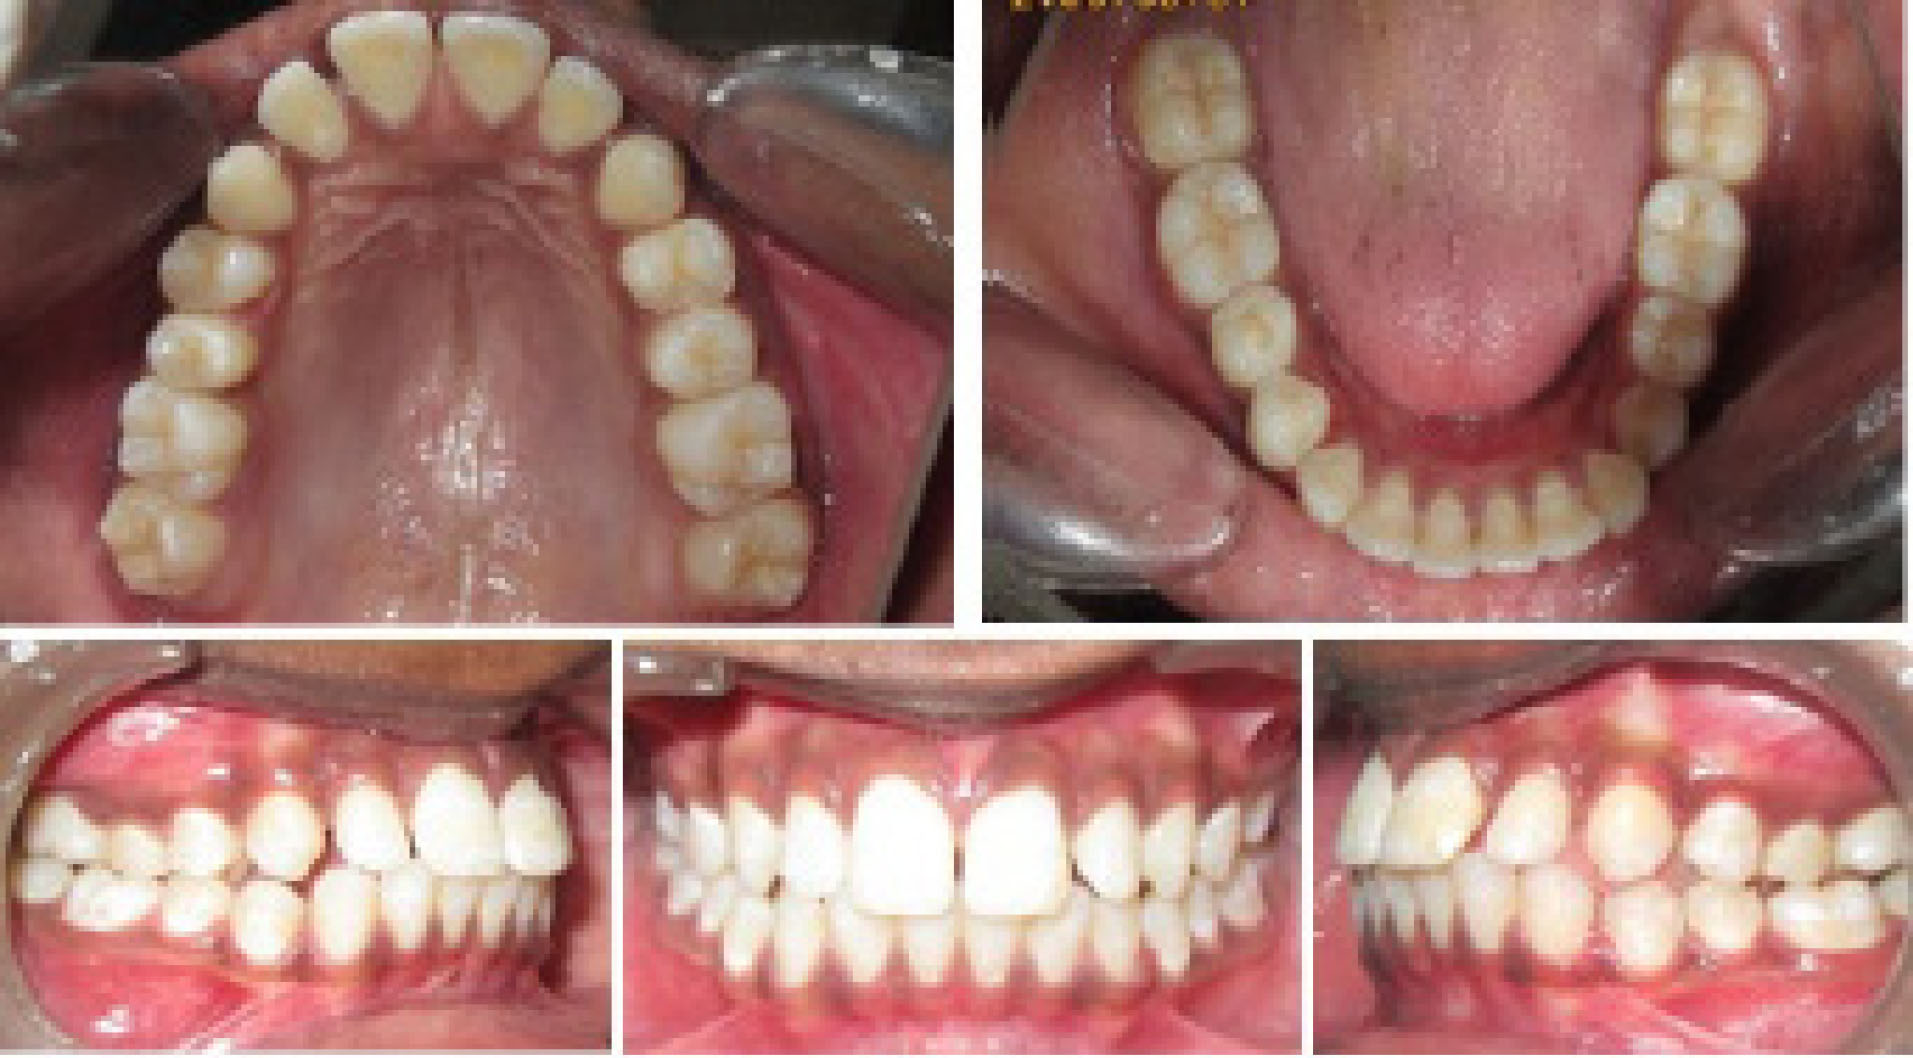

Intraoral photographs ( and ).

Intraoral photographs at T2, depicting the end of functional phase.

The anchorage design for the appliance consisted of total anchorage in the lower arch by the inclusion of teeth from the first molar on one side to the contralateral side in the lower arch, with partial anchorage in the upper arch by the inclusion of the first premolar to the first molar on each side (). Achievement of class I molar relationship marked the end of the functional phase, and a change in the molar relationship was assessed easily by removing the tubes and plunger. Since it works by snap fit over the ball joints, removal and insertion are quite easy.

FFAs are fixed to the teeth, and invariably, some amount of dental changes occur, and the total therapeutic change in any functional therapy is the result of a combination of skeletal and dental correction that takes place. The achievement of a class I molar relationship marked the end of the functional phase in this study. Dental changes observed in the present study were favorable towards class II correction, and upper molars and incisors moved backward; lower molars and incisors moved forward.

The upper incisor position (is/OLp) changed significantly from 83.5 mm to 79.6 mm (P< 0.001). The position of the upper incisor within the maxilla (is/OLp-ss/OLp) decreased from 11 to 9 mm (P= 0.006), suggesting a retroclination of upper incisors. Dental changes with the maxillary incisor were more pronounced compared to other studies.

This can be attributed to the anchorage design consisting of total anchorage in the mandible with partial anchorage in the maxilla. The upper molar moved distally by 1.5 mm (P= 0.058).

Lower incisor position changes (in total and within the mandible), though favorable, were not consequential. Lower molar changes were highly pronounced (P< 0.001). The lower molar position within the lower jaw changed significantly (P= 0.002). Overall dental changes in the maxilla were more than the mandible, indicating a loss of anchor in the upper arch alone due to the anchorage design.